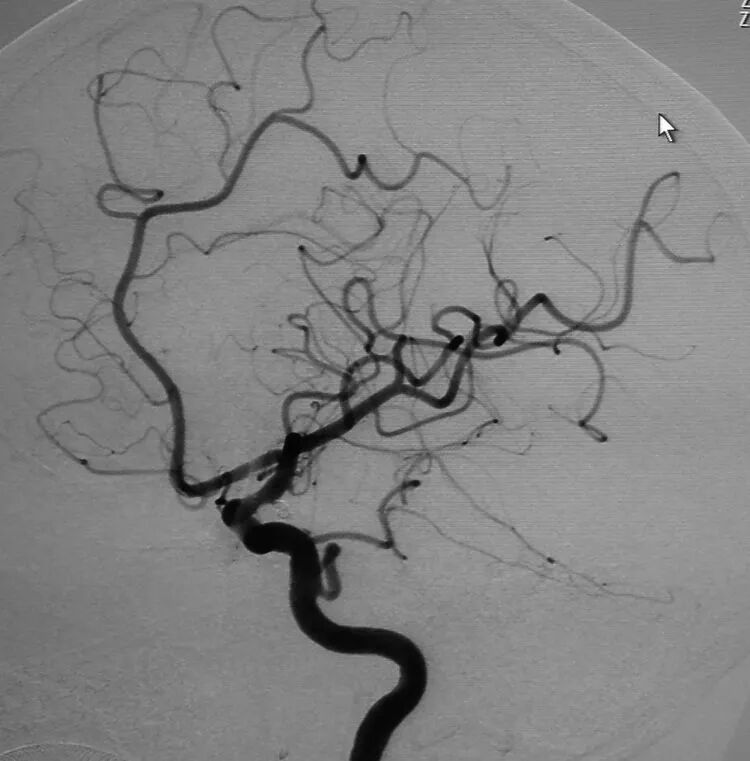

基底动脉顶端动脉瘤,瘤体长轴跟基底动脉主干平行

典型病例2